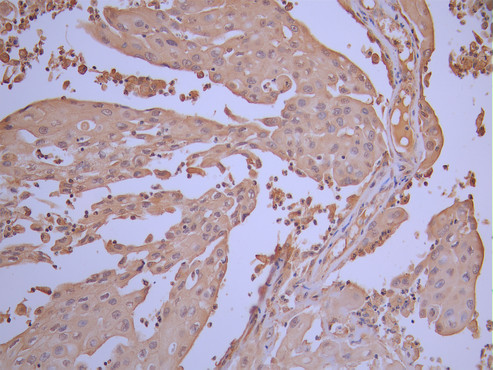

• IHC image of CSB-RA091918A0HU diluted at 1:100 and staining in paraffin-embedded human cervical cancer performed on a Leica BondTM system. After dewaxing and hydration, antigen retrieval was mediated by high pressure in a citrate buffer (pH 6.0). Section was blocked with 10% normal goat serum 30min at RT. Then primary antibody (1% BSA) was incubated at 4°C overnight. The primary is detected by a Goat anti-rabbit polymer IgG labeled by HRP and visualized using 0.05% DAB.